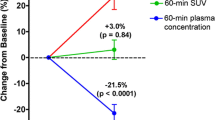

Similar to before treatment, there was a wide range in 18F-uptake (SUVA50%) after treatment (2.71–37.67; median 11.84). Treatment did not affect 18F-uptake, when considering the median 18F-uptake of all involved lesions before and after treatment (11.74 vs 11.84, p = 0.61). However, a detailed analysis of individual patients revealed that the difference in 18F-uptake before and after treatment not only varied between patients (from −2.20 to 4.53 (median 0.48)) (Fig. 3, Table 1) but also between different lesions within the same patient. For example, in BBR04, 18F-uptake in the posterior iliac crest increased from 5.86 to 10.6 (ratio 1.81), with a concomitant increase in MAR from 0 to 1.37, while the BF in the MM-related bone lesions did not improve (ratios 0.77–1.02) (Fig. 3). In only one patient (BBR01), a homogeneous, statistically significant increase in 18F-uptake was shown due to treatment (7.34–11.34 before and 12.50–17.49 after treatment; p = 0.043) (Fig. 3).

Thus far, there is only limited circumstantial evidence that bortezomib improves BF. Several investigators suggested an increase in BF during bortezomib treatment based on increased serum BF markers, but only Giulinani has shown an effect on patient osteoblasts. Moreover, there is debate whether this is independent from an anti-MM effect of bortezomib: although serum sclerostin (inhibiting BF) is downregulated independent of an anti-MM effect [13], the increase in the number of osteoblasts was found only in responding patients [4]. Our data, showing a pronounced inter- and intra-individual heterogeneity in BF after treatment, might explain previous controversial results in literature, as serum markers and biopsies at single sites do not reflect such anatomical diversity.